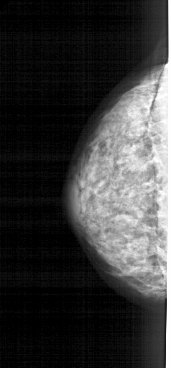

A_1269_1.RIGHT_MLO

RIGHT_MLO LINES 4726 PIXELS_PER_LINE 1831 BITS_PER_PIXEL 12 RESOLUTION 43.5 OVERLAY

FILE: A_1269_1.RIGHT_MLO.OVERLAY

TOTAL_ABNORMALITIES 1

ABNORMALITY 1

LESION_TYPE CALCIFICATION TYPE PLEOMORPHIC DISTRIBUTION CLUSTERED

ASSESSMENT 4

SUBTLETY 3

PATHOLOGY BENIGN